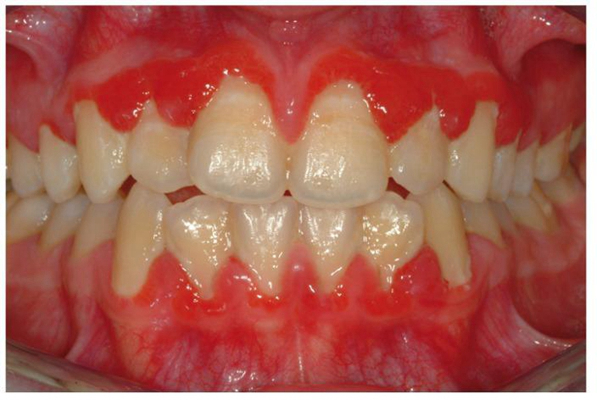

牙齦炎圖片

牙齦炎和牙周炎